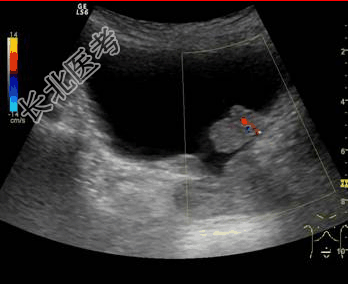

- [材料题] 患者男,72岁,因“无痛性血尿2周”来诊。超声(见下图):膀胱三角区低回声区,约20 mm×25 mm,不随体位改变而移位,形态欠规则,低回声区内见点状血流信号,基底附着处膀胱壁肌层显示不清,但外界膜显示尚清晰,膀胱充盈时肿物不向外膨出。

- 简答题1、根据声像图初步分期为?

- 简答题2、如要进一步确定肿瘤的分期,应检查?